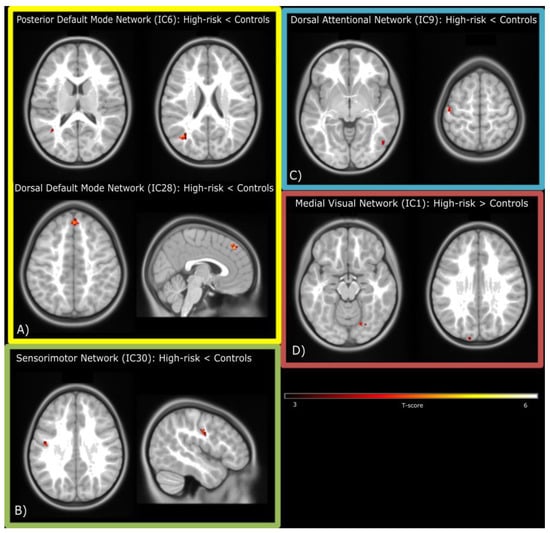

| Regions | Hemisphere | T | n Voxels | p-Value (FDR Corrected) | x | y | z |

|---|---|---|---|---|---|---|---|

| Posterior DMN (IC6): Controls > High-risk ED children | |||||||

| Angular Gyrus | Left | 4.99 | 22 | 0.048 | −38 | −66 | 22 |

| Middle Temporal Gyrus | Left | 4.61 | 31 | 0.016 | −40 | −60 | 12 |

| Dorsal DMN (IC28): Controls > High-risk ED children | |||||||

| Medial Superior Frontal Gyrus | Right | 5.8 | 52 | <0.001 | 2 | 42 | 44 |

| Sensorimotor Network (IC30): Controls > High-risk ED children | |||||||

| Postcentral Gyrus | Left | 4.7 | 25 | 0.012 | −46 | −10 | 34 |

| Attentional Network (IC9): Controls > High-risk ED children | |||||||

| Postcentral Gyrus | Left | 5.78 | 32 | 0.03 | −48 | −18 | 62 |

| Inferior Temporal Gyrus | Right | 5.22 | 24 | 0.03 | 50 | −64 | −2 |

| Visual Network (IC1): High-risk ED children > Controls | |||||||

| Fusiform Gyrus | Right | 4.79 | 21 | 0.028 | 22 | −64 | −12 |

| Superior Occipital Gyrus | Left | 4.6 | 29 | 0.024 | −14 | −100 | 26 |